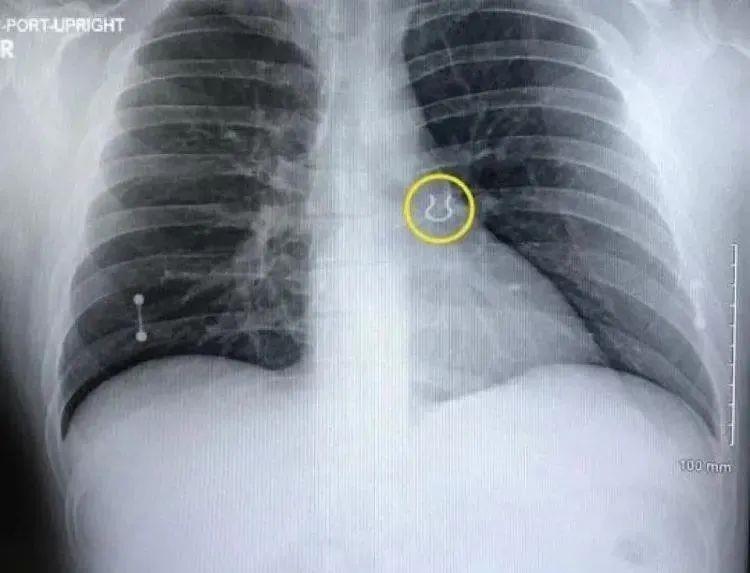

06:来自辛辛那提的穿刺爱好者乔伊·莱金斯半夜醒来,咳嗽得很厉害。感觉好像有什么东西堵住了他的呼吸道,觉得自己无法呼吸,并开始怀疑自己患有肺炎或其他严重的呼吸道疾病。莱金斯第二天去医院检查,X光片显示他的左肺上叶有异常。医生向他展示了扫描结果,这个扭曲的小物体让他大吃一惊。这是他多年前丢失的东西,找了很久都没有找到……